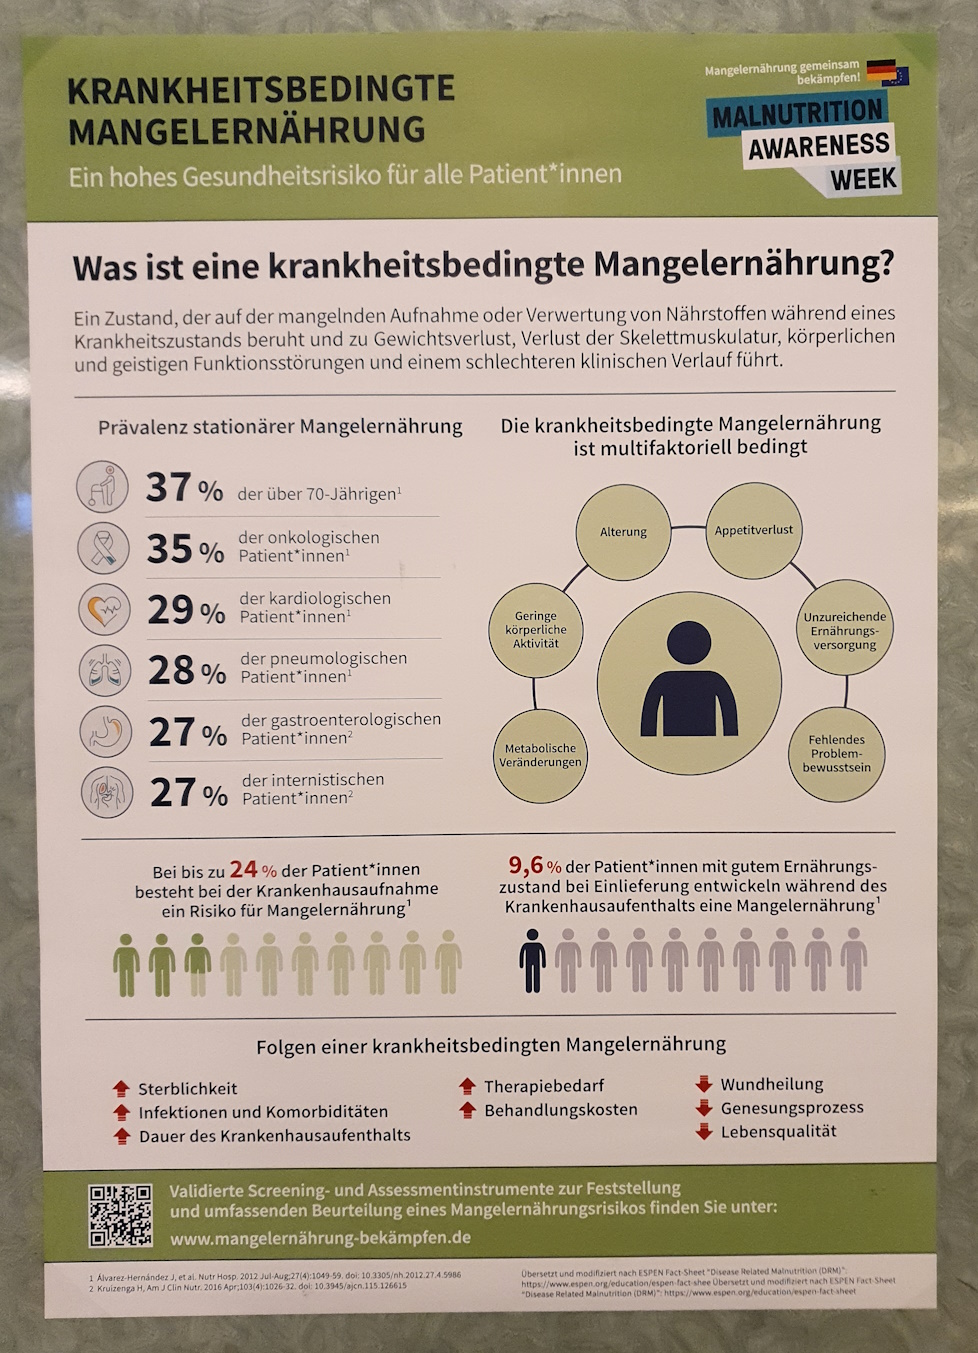

Der Weißkohl enthält Calcium, Magnesium und Kalium, die für das Nervensystem und die Muskeln und Knochen wichtig sind, viel Zink und Vitamin C, die das Immunsystem stärken, und Senfölglykoside, die entzündungshemmend und antibakteriell wirken – wichtig bei den offenen Wunden meiner Freundin. Das Krankenhaus liefert in Sachen Heilung durch Lebensmittel keine Empfehlungen – immerhin hängen überall Plakate zur allgegenwärtigen Mangelernährung.

Das Thema ist trotz all des verfügbaren Wissens und sehr populären Sendungen wie den großartigen „Ernährungsdocs“ im NDR noch nicht bei der Masse angekommen – Theorie und Praxis klaffen da maximal weit auseinander. Da ich als selbst Betroffener jahrelang eine große Internet-Kochgruppe für Schwerkranke leitete („Iss Dich gesünder“), weiß ich, dass sich Ernährungsgewohnheiten nur sehr mühsam ändern lassen und die meisten am Ende lieber dauerkrank bleiben als irgendetwas anders zu machen (zuvor wird meist noch vergeblich und oft kontraproduktiv mit Nahrungsergänzungsmitteln herumexperimentiert) – liest sich einigermaßen seltsam, ist aber so.